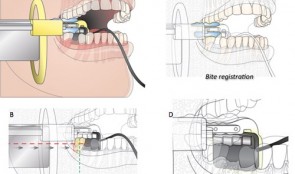

Analytical Methods: Imaging

based on the book chapter by Erika Benavides and Hector F. Rios Summary Clinical imaging allows qualitative and quantitative assessment of hard and soft oral tissues in patients after procedures such as ridge augmentation. This comprehensive guide deals with in vivo and ex vivo and intraoral and extraoral methods. It covers standardized digital intraoral radiography, cone beam (CBCT) and multislice (MSCT) computed tomography, subtraction radiography, ultrasound, optical coherence tomography (OCT), and newer methods such as CAD/CAM (computer-aided design/computer-aided manufacturing) and fractal analysis. There are descriptions on how each modality words, and outlines of their common applications, relative merits and limitations. Among the issues addressed are wave type (e.g infrared versus ionizing radiation), signal noise, distortion, mage resolution, field of view, scanning time, patient trauma and artifacts such as beam-hardening. Illustrations are used throughout to clarify the discussion. The authors point out which methods are preferable for macrostructure, and which for microstructure; for mineralized tissues, and which for soft tissue contours. Some are better for revealing the functions and dynamics of tissues or volumetric changes; some are better at 3-D visualizations and complex typography; some involve exposing patients to ionizing radiation. The authors stress the importance of integrating information from different modalities (such as CAD/CAM with CBCT) and from different time points, to optimize information available for interpretation. Open full-text PDF (1.8 MB) -